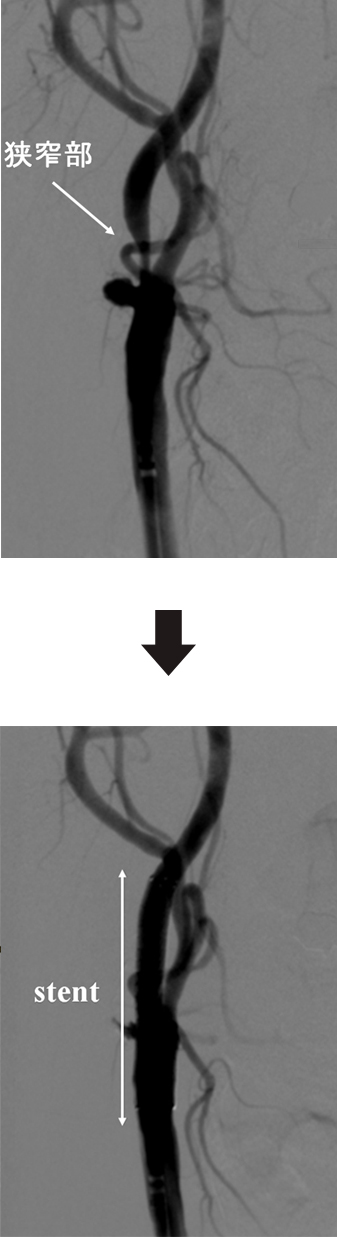

頚動脈狭窄は、過去に脳梗塞や一過性脳虚血発作の既往がある症候性頚動脈狭窄と既往のない無症候頚動脈狭窄があります。一般的に症候性の場合は50%以上の狭窄、無症候性の場合は80%以上の狭窄で治療適応の検討が必要です。治療方法は外科的に狭窄部を取り出す内頚動脈剥離術(CEA)と狭窄部をステントで拡張する頚動脈ステント留置術(CAS)があります。

当院で行う頚動脈ステント留置術(CAS)は、局所麻酔下に、足の付け根の血管(大腿動脈)からカテーテルを通して、血管の中から狭窄部位を広げる治療です。頚動脈の狭窄部分に“ステント”と呼ばれる金属性の網状の筒を留置して、血管を正常径まで拡張させる手術です。血管を拡張させる時に、コレステロールの破片や血栓が脳内に流れて行くと脳梗塞を生じてしまいます。そこで脳梗塞の予防のためには、小さな特殊な網(フィルター)をあらかじめ狭窄部位の先に進めておいて、治療中に血流を止めることなく、コレステロールの破片や血栓だけを回収して、脳梗塞を起こすことを予防します。また小さなバルーンで一時的に血流を遮断してから治療を行うこともあります。

この治療は、内膜剥離術と比較して非侵襲的であり、高齢者やいろいろな合併症を持った方にも負担を少なくして行うことができます。術後の安静期間や入院期間も短いのが特徴です。また「CAS 実施医」「CAS 指導医」という制度も設けられ、この制度によって、頸動脈撮影の経験と所定の研修コースを修了した医師にのみ、治療の資格が与えられています。現在当院では脳神経外科で施行しております。